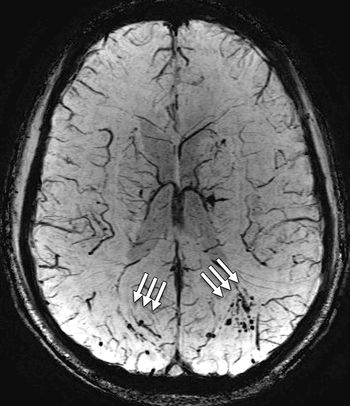

Brain MRIs may help diagnose vascular cognitive disorder following strokes and TIAs.